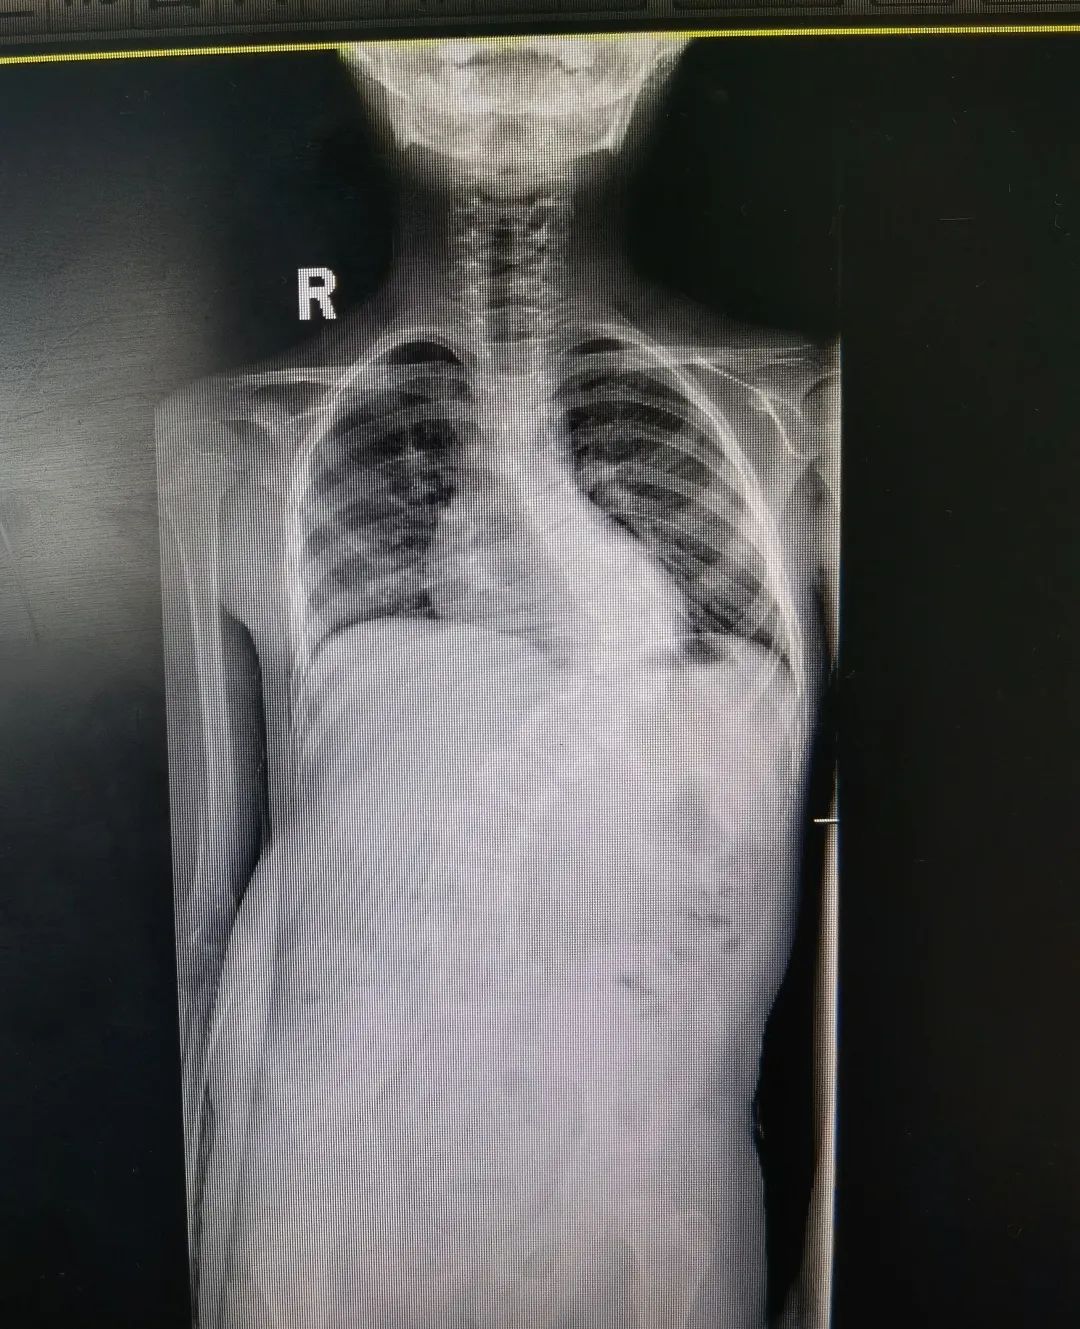

马凡综合征引起的脊柱侧弯术前术后图

“马凡综合征是一种常染色体显性遗传性结缔组织病,具有家族集聚性,可影响全身的结缔组织,有些孩子会出现脊柱侧弯的情况。”

陈文昊副主任表示,由于马凡综合征患儿骨骼发育异常,给手术增加了一定难度,但手术结果很不错的,达到了预期效果。他还指出一个自测马凡综合征的小妙招,让孩子把大拇指包住握拳,如果大拇指不能完全被包住,露出前面关节,家长就要当心了,建议去医院做进一步检查。